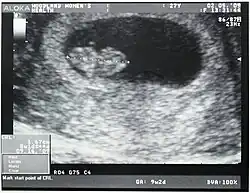

Crown-rump length

Crown-rump length (CRL) is the measurement of the length of human embryos and fetuses from the top of the head (crown) to the bottom of the buttocks (rump). It is typically determined from ultrasound imagery and can be used to estimate gestational age.

The embryo and fetus float in the amniotic fluid inside the uterus of the mother usually in a curved posture resembling the letter C. The measurement can actually vary slightly if the fetus is temporarily stretching (straightening) its body. The measurement needs to be in the natural state with an unstretched body which is actually C shaped. The measurement of CRL is useful in determining the gestational age (menstrual age starting from the first day of the last menstrual period) and thus the expected date of delivery (EDD). Different human fetuses grow at different rates and thus the gestational age is an approximation. Recent evidence has indicated that CRL growth (and thus the approximation of gestational age) may be influenced by maternal factors such as age, smoking, and folic acid intake. Early in pregnancy gestational age 8 weeks, it is accurate within about +/- 5 days but later in pregnancy, due to different growth rates, the accuracy is lower. In that situation, other parameters can be used in addition to CRL. The length of the umbilical cord is approximately equal to the CRL throughout pregnancy.